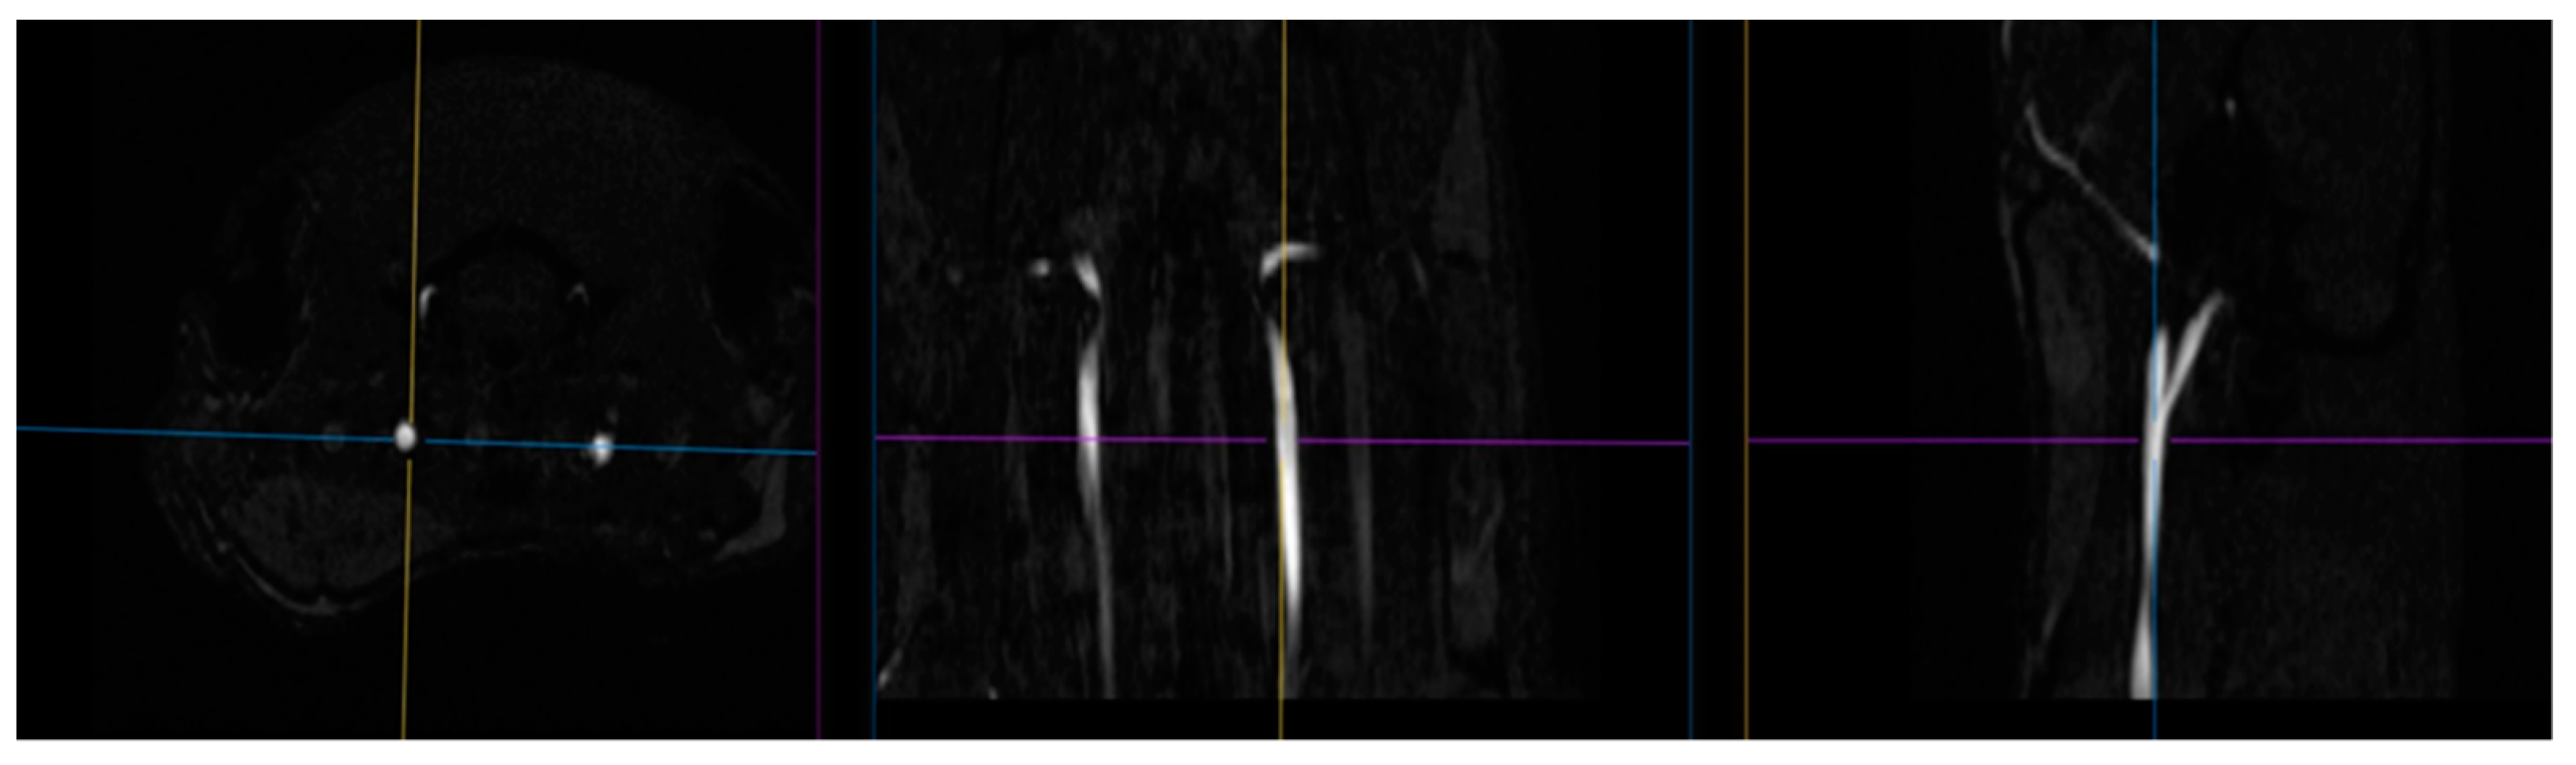

The blood supply of the brain was examined using time of flight (TOF) angiography in one scan session with MRI [56,57]. Images of the common carotid arteries (left and right; Figure 14) were obtained in a two-dimensional projection (an example is shown in Figure 15), which, by means of the ParaVision5.1 MIP (maximum intensity projection) option, were converted into 3D images. The measurement of the size of the vessels was performed using an ROI placed 2 mm proximal to the bifurcations of the carotid arteries, which were determined from 3D images. Along with the imaging of angioarchitectonics, the blood flow velocity was assessed by the method of phase contrast angiography PCA (phase contrast angiography). The measurement was performed in a single cross-sectional main blood flow section, also guided by a 3D model (an example of PCA phase contrast angiography is shown in Figure 2). We performed these measurements 2 mm proximal to the bifurcations of the carotid arteries, that is, in full accordance with the area of measurement of dimensions of the vessels’ lumen. Additionally, the maximum blood flow velocity in the central part of the artery and the average linear blood flow velocity for the entire section of the lumen of the artery were determined. Volumetric blood flow (mL/min) was calculated based on the mean blood flow velocity and cross-section. All hemodynamic characteristics were obtained in a 2 min recording interval with averaged values as a result of several complete heartbeat cycles. The following indicators were used in the paper: the speed of blood flow in the left and right common carotid arteries (velocity of OSA L, cm/s; velocity of OSA P, cm/s); the area of the lumen of the left and right common carotid arteries (lumen o.s.a. L, mm2; lumen o.s.a. P, mm2); volumetric blood flow of the left/right common carotid artery and their sum score (o.s.a. blood flow L, mL/min; o.s.a. P blood flow, mL/min; o.s.a. blood flow, mL/min).

Figure 15. (Left) 2D TOF image of carotid arteries; (right) 2D image of the same area obtained using PCA.